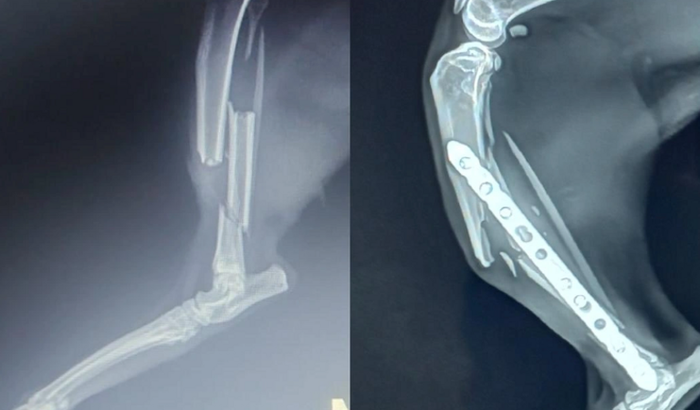

Essa gatinha sobreviveu a essa queda enorme, operou, colocou uma placa e sete pinos e, mesmo com todos os cuidados do mundo, a recuperação dela não foi boa. As fotos da vakinha são do dia que ela quebrou e como está agora. Pra falar a verdade, cada dia que passa, a patinha dela quebra um pouco mais só com ela mexendo para o básico (comer, beber água, etc.)

O que acontece é que arcar com os custos da primeira cirurgia já não foi muito fácil, mas chegar com outra em apenas um mês é impossível pro nosso orçamento. Se não fizermos essa nova cirurgia de correção com urgência, ela vai acabar tendo que amputar a patinha…